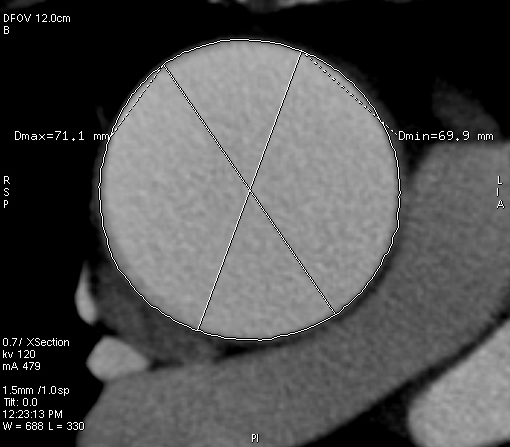

ANEURISMI

IMMAGINI DI ANEURISMI E INTERVENTI RELATIVI

CARDIO IMAGING

immagini significative del cuore e dei grossi vasi

coronaro TC